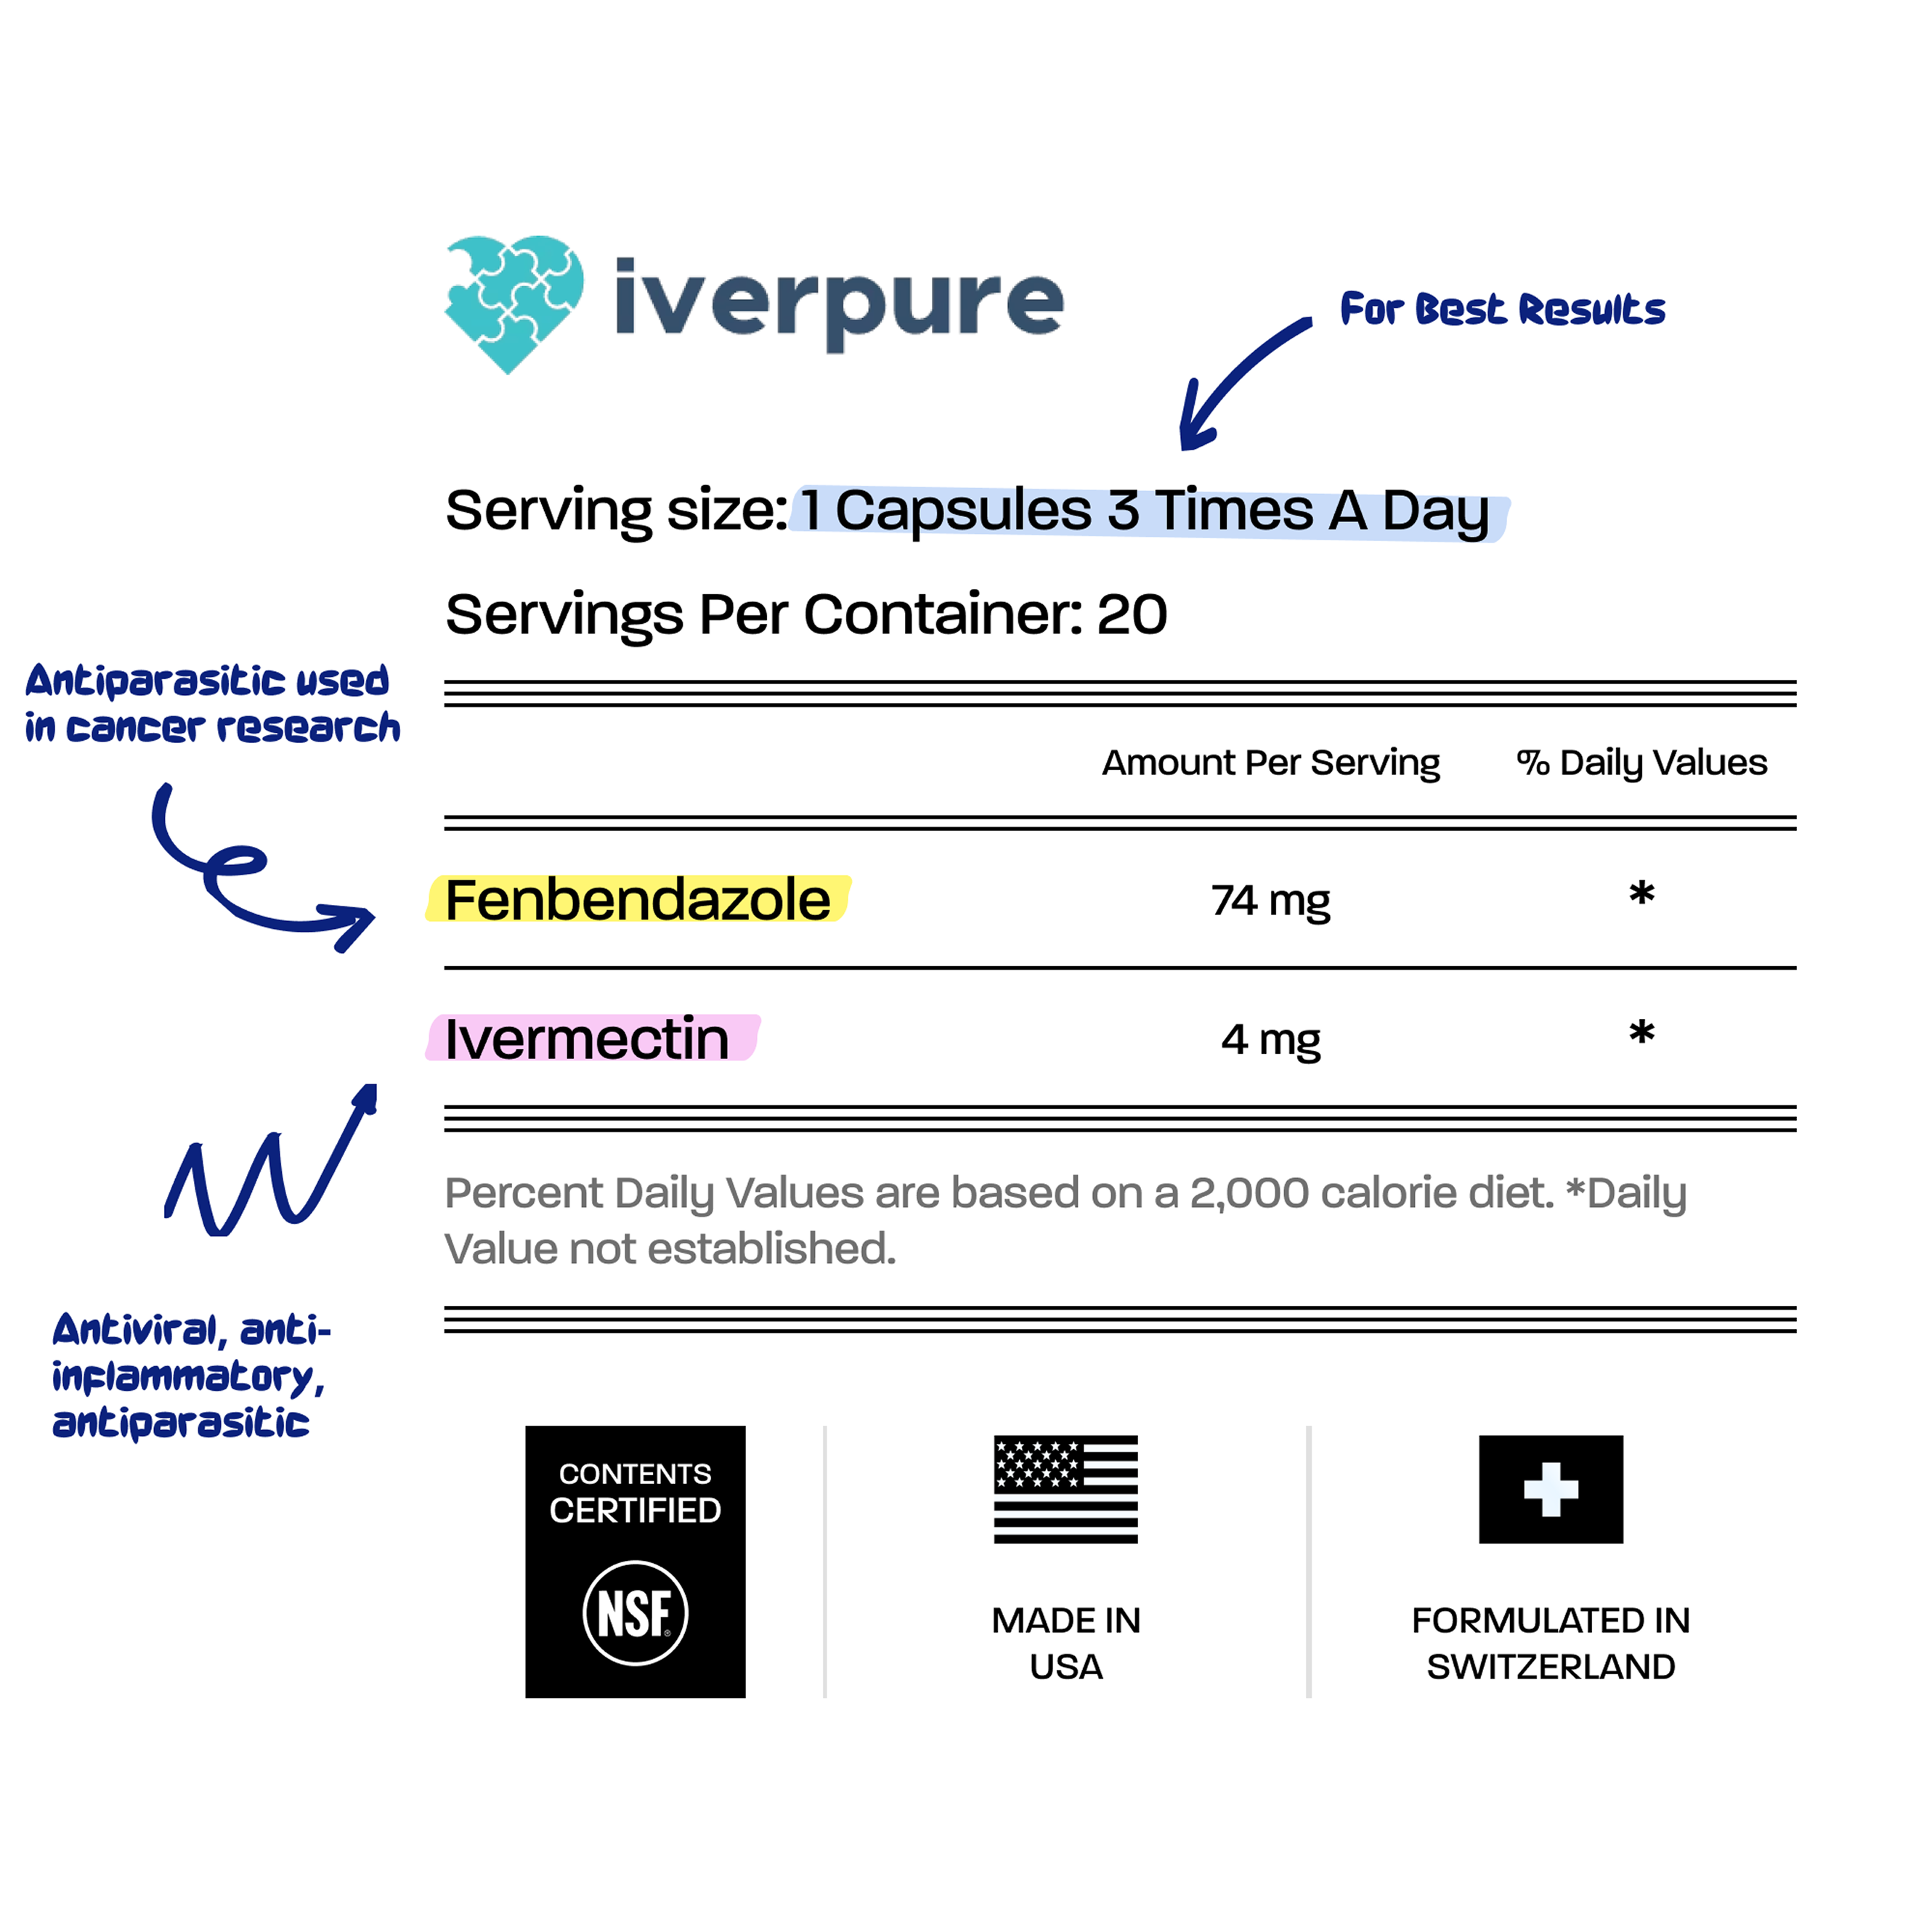

Clinically trusted for decades, Ivermectin helps bind and flush out parasites, biofilm waste, and immune disruptors hiding deep in tissues. Our formula uses only the purest medical-grade Ivermectin—no fillers, no toxins.

Fenbendazole is a well-researched anti-parasitic compound known for its powerful detox and cellular repair support. Backed by emerging science, it’s used for everything from gut resilience to systemic cleanup.

Take 1 capsule 3 times daily with meals. For best results, maintain consistent timing and follow the recommended dosage. Consult with your healthcare provider before starting any new supplement regimen.

Crafted with premium and lab-tested Ivermectin and Fenbendazole to help your body flush out unwanted toxins and support optimal gut and immune health.